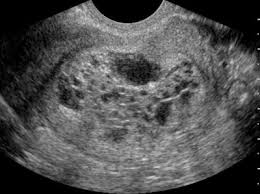

Kehamilan ektopik mengandung luar rahim ini juga lebih dikenali sebagai kehamilan ektopik di mana janin pada kebiasaannya akan melekat dan membesar di tiub fallopio. Semua pasangan berkahwin pasti mahukan fasa kehamilan berjalan lancar sehingga sampai waktu untuk bersalin. Hamil di luar kandungan atau dalam istilah medis dikenal dengan kehamilan ektopik, terjadi ketika sel telur yang sudah dibuahi tidak menempel pada rahim, melainkan melekat di dinding saluran tuba falopi, rongga perut, indung telur (ovarium), atau leher rahim (serviks). Jika ini berlaku, ia adalah sangat bahaya dan boleh mengancam nyawa anda. Namun tidak semua kehamilan berjalan seperti ini karena ada beberapa kehamilan yang terjadi di luar kandungan atau luar rahim.

Namun tidak semua kehamilan berjalan seperti ini karena ada beberapa kehamilan yang terjadi di luar kandungan atau luar rahim. Bagian rahim juga dapat dilihat apakah mengalami pembesaran layaknya kehamilan pada umumnya atau tidak. Namun begitu, sesiapa saja berisiko untuk mengalami komplikasi kehamilan. By the time aku pergi pd, memang dah tak rasa pun. Kehamilan ektopik mengandung luar rahim ini juga lebih dikenali sebagai kehamilan ektopik di mana janin pada kebiasaannya akan melekat dan membesar di tiub fallopio. Haid lewat, sakit bawah perut dan pendarahan… Ibu, 29 tahun, mengandung kali ke 3, usia kandungan 10 minggu, datang ke unit kecemasan kerana sakit perut yang teruk secara tiba tiba hingga tidak boleh berjalan. Sakit senggugut aku tu slowly hilang. Ini terjadi apabila telur yang tersenyawa membuat implantasi di luar rahim. Jom kami kongsikan info tentang mengandung luar rahim. Terkadang kehamilan juga bisa terjadi pada bagian luar rahin atau bahkan menempel pada usus. Semua pasangan berkahwin pasti mahukan fasa kehamilan berjalan lancar sehingga sampai waktu untuk bersalin. Doc check mmg saya peknen 7 minggu, tp luar rahim.

Tindakan medis kedua untuk mendeteksi hamil di luar kandungan adalah dengan melakukan pemeriksaan panggul. Ada yang tidak berdepan simptom langsung, ada yang mempunyai pelbagai simptom. Dalam beberapa minggu hingga bulan ia dapat tumbuh di sana namun tidak dapat menjadi janin karena sejatinya tempat yang cocok hanyalah rahim. Salur fallopian akan mengembang dan akhirnya pecah dan menyebabkan perdarahan dalaman yang serius. Aku ada sakit perut tapi tak sharp pain. 10 tanda tanda hamil diluar kandungan paling jelas. Memang tak nampak sangat ada kat aku. Bagi kes kehamilan luar rahim, ia dianggarkan boleh berlaku kepada 1 dalam 50 ibu mengandung.